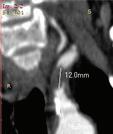

между m. constrictor pharyngis и горния полюс на тонзилата или между тонзиларната капсула и задната небна дъга (Фиг. 4). При него се изолира полимикробна флора. Преобладаващите организми са анаероби: Prevotella, Porphyromonas, Fusobacterium и Peptostreptococcus; аероби са: група А Streptococcus β-хемолитичен стрептокок, Стафилококус ауреус и Хемофи -

-

инфлуенца. Клинически се

на едната тонзила медиално, тризъм, „гъгнив” глас, повторно

ма се

за

изследване и се започва антибиотично лечение. В първите 2-3 дни, ако инцизията се е

и абсцес-тонзилектомия под

протекцията на масивни дози антибиотици. С оглед запазване на функцията на незасегнатата сливица при децата под 6 г. се съветва да се от-

страни само засегната сливица. След стихване на възпалителните изменения - 4 до 6 седмици е желателно да

бъде проведена тонзилектомия. Перитонзиларният абсцес може да доведе до застрашаващи живота на

детето усложнения: ретро- и парафа -

рингеален абсцес, медиастинит, тонзилогенен сепсис.